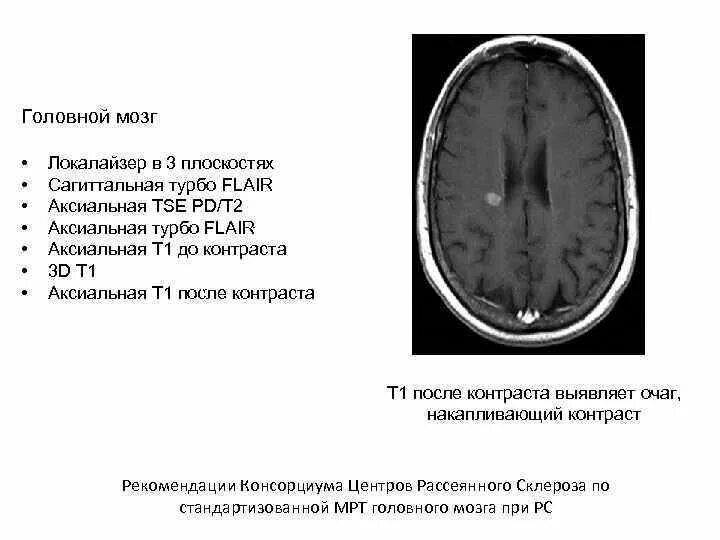

Демиелинизирующее заболевание головного мозга что это такое